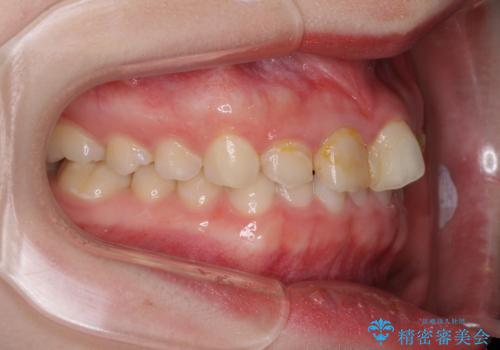

上下前歯の歯列不正はインビザラインにより歯列を整え、その後に、前歯5本をオールセラミッククラウンにて補綴治療することとしました。

矯正治療にて歯並びを整えた後に、虫歯の大きかった5本の歯をセラミッククラウンにて補綴し、明るい口元になりました。